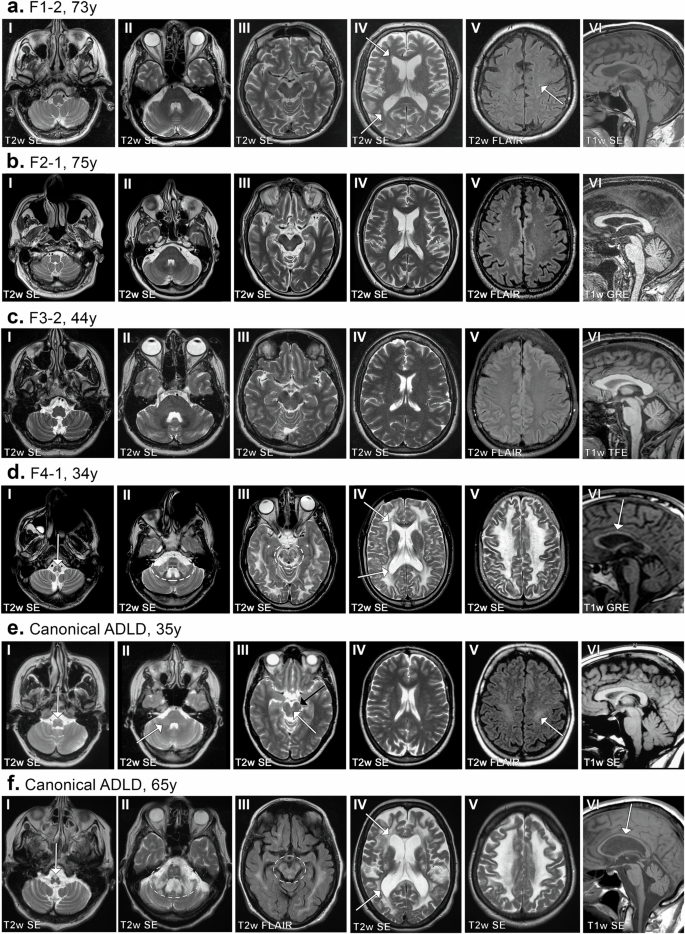

Genomic duplications of chr5q23.2, encompassing LMNB1, were initially identified in three independent multi-generational families (families F1-F3, Supplementary Fig. 1a–c) by whole genome wide array comparative genomic hybridization (aCGH) studies. A detailed description of the ages and clinical phenotypes of individuals with the duplications are provided in Supplementary clinical data and Table 1. Adult subjects from families F1-F3 had mean and median ages of 62 and 65 years, respectively (range—48–84 years). Magnetic resonance imaging (MRI), a key tool for the diagnosis of leukodystrophies, revealed that none of these individuals exhibited leukodystrophic changes (Fig. 1a–c). MRI abnormalities have been shown to precede neurological symptoms in ADLD (Fig. 1e) and can be identified as early as 29 years of age18. The mean and median ages at onset for ADLD patients from previous studies were estimated to be 47 and 48 years, respectively (range—40–58 years), while the mean and median ages at death were 66 and 68 years, respectively (range—56–75 years)18. The fact that the older subjects from F1-F3 with the duplications did not exhibit any MRI abnormalities or significant disability even in their mid-70s (Fig. 1a, b), an age at which no ADLD patients live beyond, further supports that they do not suffer from ADLD. Interestingly, although individuals did not exhibit the demyelination phenotype, some of them exhibited symptoms such as intermittent bowel or bladder dysfunction or orthostatic hypotension which can both be part of the early autonomic symptoms in ADLD (Table 1, Supplementary clinical data).

Images I-V are axial slices of the brain and images VI parts of the middle sagittal slices. Subjects of the families F1, F2, and F3 did not exhibit leukodystrophic changes (a–c), but the oldest subjects had age-related hyperintensities, best seen in F1-2 periventricularly (a.IV, arrows) and as small foci in deep white matter (a.V, one marked with an arrow). Subject F4-1 showed a pathologic high signal intensity in the pyramids of the medulla oblongata (d.I, arrow), in the pons and middle cerebellar peduncles (d.II), mesencephalon (d.III), and in all cerebral lobes (d.III-V). A less affected periventricular rim in T2w SE images (d.IV, arrows) is characteristic for LMNB1-related leukodystrophy. The corpus callosum is thin (d.VI, arrow). For comparison, images of two subjects from other families with a canonical ADLD-causing LMNB1 duplication are presented (e, f). The subject at the age 35 was still asymptomatic but had a mild T2 signal intensity increase in the pyramids (e.I, arrow), in the middle and upper cerebellar peduncles (e.II-III, white arrows), and in the corticospinal tracts both in the mesencephalic (e.III, black arrow) and uppermost parts (e.V, arrow). The other subject was 65 years old and had a clinical disease. She exhibited similar MR abnormalities to those in F4-1. A pathologic high signal intensity in the pyramids of the medulla oblongata (f.I, arrow), in the pons and cerebellar peduncles (f.II), mesencephalon (f.III), and in all cerebral lobes (f.III-V). A less affected periventricular rim is seen in T2w SE images (f.IV, arrows) and the corpus callosum is thin (f.VI, arrow). Abbreviations: T2w T2-weighted, T1w T1-weighted, SE spin echo sequence, FLAIR fluid attenuated inversion recovery sequence, GRE gradient echo sequence, TFE turbo field echo sequence.

The exception to this range was the F4-1 patient that we previously identified5 (Supplementary Fig. 1d, denoted as BR-1 in that publication) with a duplication of ~475 kb involving LMNB1 but whose clinical features had not been previously described. This patient did not have a head-to-tail tandem duplication but rather an inverted duplication (ADLD-Inv-Dup) that was inserted centromeric to the LMNB1 gene (Fig. 2a)5. F4-1 exhibited, both clinically and radiologically, a more severe and accelerated form of ADLD with MRI features at age 34 (Fig. 1d, Supplementary clinical data) resembling ADLD patients in their 60s with advanced stages of the disease (Fig. 1f) and was wheelchair-bound at age 38. Furthermore, both his mother and grandmother were reported to have suffered from a similar neurological disorder and died in their mid 30s (Supplementary Fig. 1, Supplementary clinical data).